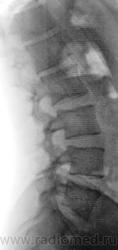

Деформация передне-нижнего отдела L1 позвонка. Да и Th12 сомнительно. Сделал бы прицельно и при необходимости резанул бы.

Похоже на грыжу Шморля L1-2 и spina bifida S1

Листеза нет?